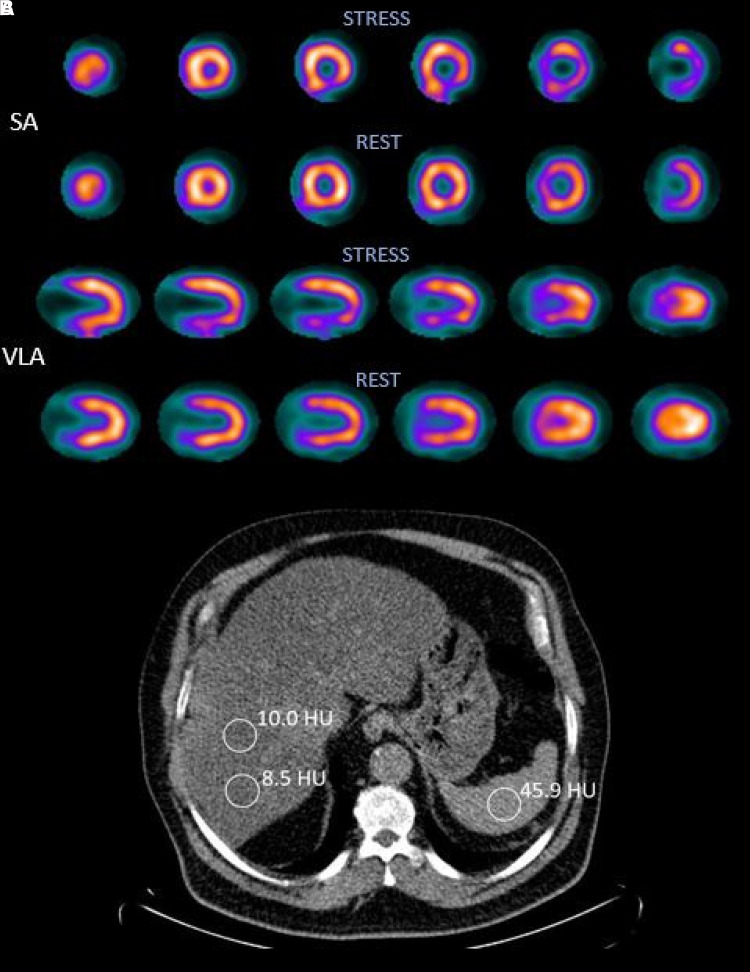

Methods and results: We analysed 742 patients who had undergone MPI using single photon emission computed tomography (SPECT) and LDCT. A liver-to-spleen ratio (in Hounsfield units) of <1 was defined as FLD. Myocardial ischaemia was defined as a summed difference score (SDS) ≥3. Left ventricular size and systolic function were assessed from the electrocardiogram-gated SPECT. FLD patients were younger (63 vs. 68 years) and had a higher body mass index (34.6 vs. 29.0 kg/m2) and a higher SDS (2.65 vs. 1.63), P < 0.001 for all. Independently of several possible confounding factors including traditional risk factors, patients with FLD had a 1.70-fold risk of ischaemia (95% confidence interval 1.11-2.58, P = 0.014). Left ventricular end-diastolic volume (109 vs. 109 mL) and ejection fraction (61 vs. 61%) were comparable in those with and without FLD (non-significant for both).

Conclusions: With the help of LDCT, it is possible to identify FLD, which is associated with an increased risk of myocardial ischaemia. Therefore, evaluation of FLD from LDCT is recommended along with MPI.